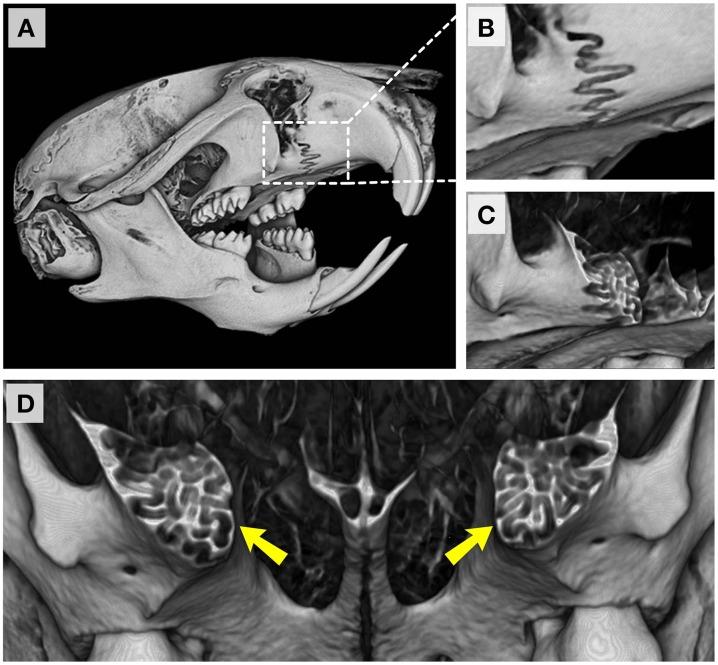

Growth of the craniofacial skeleton is a complex process controlled by both genetic and epigenetic factors, perturbations of which can lead to varying degrees of dysmorphology. Mouse models that recapitulate clinical craniofacial phenotypes are instrumental in studying the morphogenetic progression of diseases as well as uncovering their genetic and molecular bases. Commonly encountered phenotypes in these models include defects in the cranial base synchondroses, calvarial sutures, mandible or the midface, or any combination thereof, with the concurrent presence of altered overall craniofacial growth. However, the literature lacks an adequate normative timeline of developmental events and growth trends that shape the mouse craniofacial skeleton. In this report, we analyzed the postnatal craniofacial ontogeny (from postnatal day 7 [P7] through to P112) of male mice from the most widely used inbred mouse strain, C57BL/6J, using high-resolution microcomputed tomography (μCT) in combination with classic morphometric approaches. We also evaluated cranial base synchondroses at the histological level, and compared it to μCT-generated data to assess the timing and pattern of closure of these structures. Our data underscore the complex and unique growth patterns of individual bones and cranial regions and highlight the need to include younger animals in studies aimed at analyzing craniofacial growth processes. Furthermore, these data serve as a reference standard for future quantitative work.